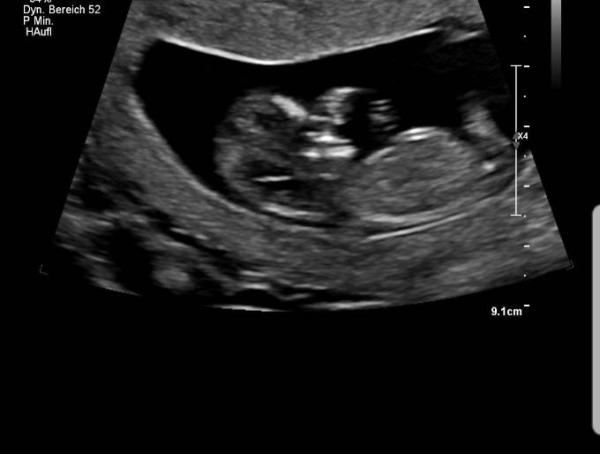

Hallo zusammen :) Ich bin ab morgen in der 14. Ssw. Ich habe jetzt vor kurzem festgestellt, dass ich immer wieder total Kurzatmig bin und sogar herzrasen bekomme wenn ich ein paar Stufen hochgehen muss z.b. am Bahnhof oder so. Geht es euch auch so? Ansonsten geht es uns total super. Die kleine Maus ist topfit. Unser Arzt hat sogar eine NFT gemacht ohne sie in Rechnung zu stellen. Und alles war blendend. Liebe Grüße

Bild zu Herzrasen - Forum für April - Mamis